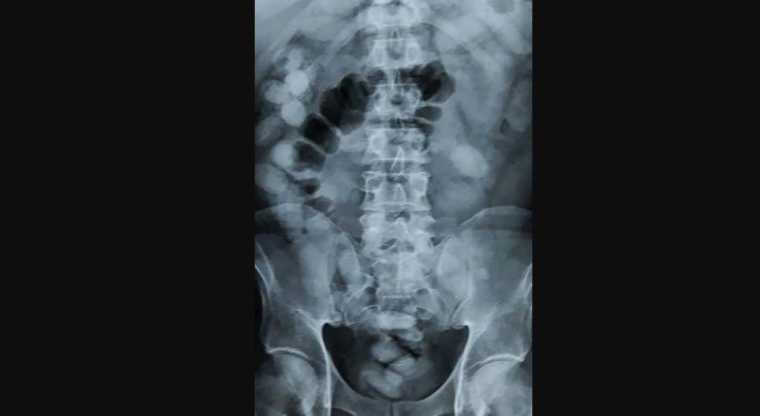

“An x-ray showed she had swallowed 1.2kg of cocaine in a bid to avoid detection,” Niyom Termsrisuk, a Thai official said.